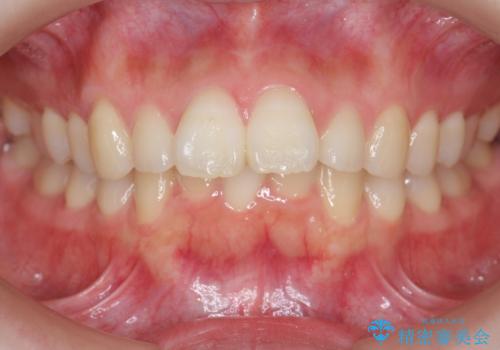

インビザラインで目立たない矯正 ガタガタの歯並びをきれいな歯並びへ